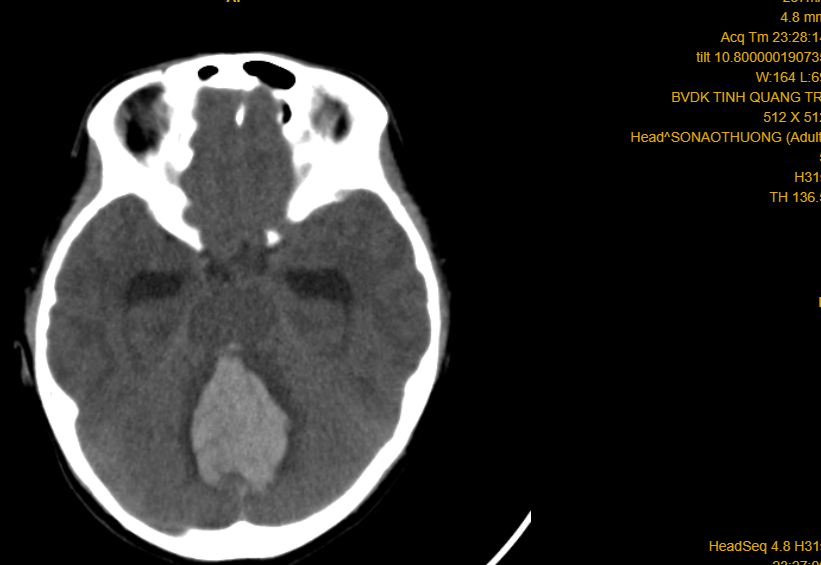

Phim CT-scan trường hợp số 01 (doanh nhân 57 tuổi) xuất huyết não